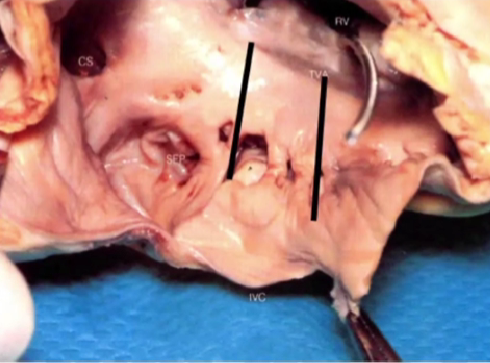

三尖瓣峡部的解剖

峡部肌束分布多连续性

后侧视角的三尖瓣峡部

1)冠状静脉窦(Coronary Sinus):位于心脏后下部,收集来自心脏大部分区域的血液。

2)三尖瓣隔叶(Septal Tricuspid Leaflet):三尖瓣的一部分,位于间隔隔侧(心室间隔)附近。

3)欧式嵴(Eustachian Ridge):位于右心房,一条突出的肌肉结构,为冠状窦口和卵圆窝的分界。

4)欧氏瓣(Eustachian Valve):右心房下腔静脉口前缘遗留下的一个下腔静脉瓣。

5)下腔静脉(Inferior Vena Cava):将血液从下肢运回心脏。

6)峡部(Isthmus):这里指的是三尖瓣峡部(Cavotricuspid Isthmus)。

7)右冠状动脉(Right Coronary Artery)。

8)三尖瓣小叶(Tricuspid Leaflet)。

9)右心房(Right Atrial Appendage)。

10)右心室(Right Ventricle)。

11)下腔静脉后壁(Posterior Vena Cava)。

12)三尖瓣瓣环(Tricuspid Valve Annulus)。

13)三尖瓣下叶(Inferior "Posterior" Tricuspid Leaflet)。

节选译自:Atlas of Interventional Electrophysiology,2024.